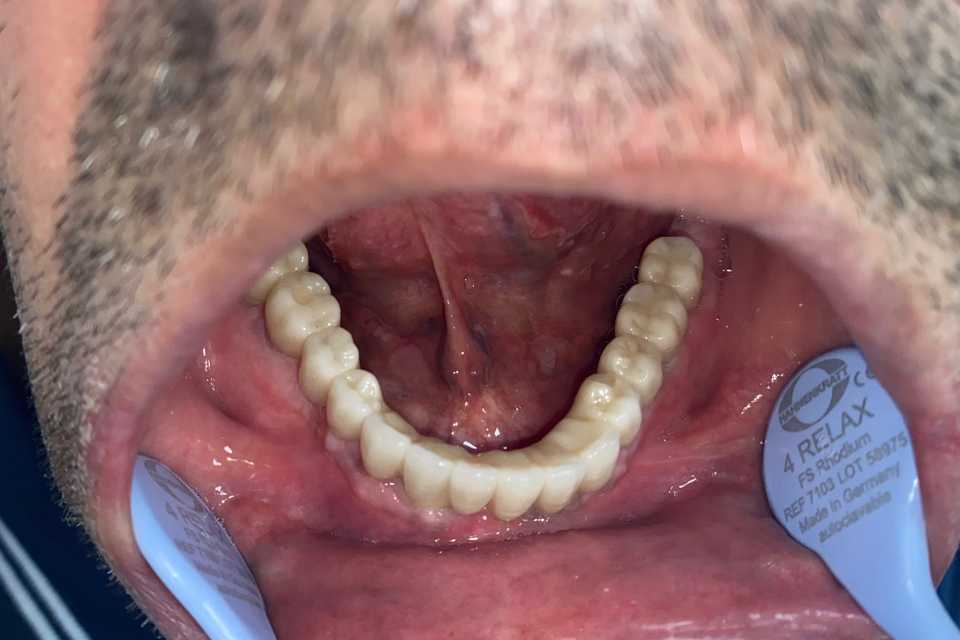

Pacientul Nicu D., în vârstă de 50 de ani, s-a prezentat în cabinet cu o edentație totală mandibulară în urma unei boli parodontale.

Împreună cu pacientul am hotărât realizarea unei lucrări protetice fixe inșurubabile pe 6 implanturi (implanturi Paltop). Lucrarea a fost realizată din ceramică pe zirconiu.

Implantul Paltop oferă posibilitatea realizării unor lucrări cu o estetică impecabilă și o afectare minimă a țesuturilor la locul implantării. Profilul concav al bontului protetic ajută la formarea unui țesut gingival dens la nivelul legăturii transgingivale scăzând vizibilitatea bontului.